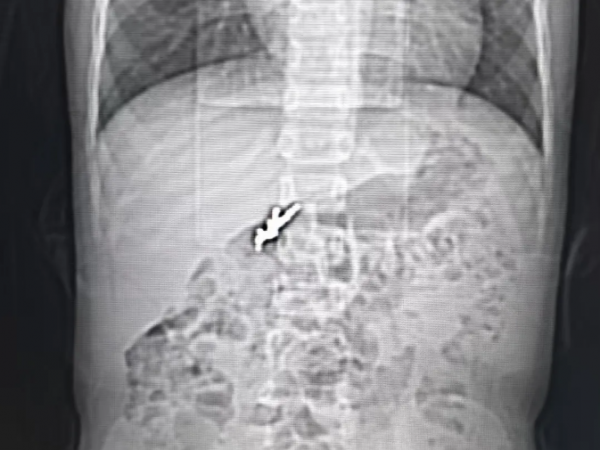

发现右部肺炎叶有5cm的结节

许主任介绍,肺结节的癌变与其形态、数量、大小、增长速度、位置等因素有关,肺结节癌变通常有3个特征,直径大于15mm实质性结节或直径大于8mm的混合磨玻璃结节。其中,结节越不规则,癌变的可能性越大,比如毛刺、分叉等。发现结节,定期检查,结节生长过快也要注意癌变的可能性发生。